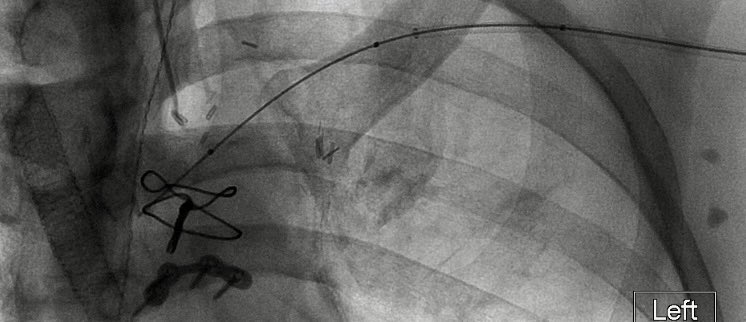

.@LucasRCmd, MPH; @HiroSparks, MD; Kara E. Masterson, MSN, NP; Scott J. Genshaft, MD; @AdamPlotnik, MD; and Siddharth A. Padia, MD, contributed to this open access article. See what they've been working on! brnw.ch/21wPx6v